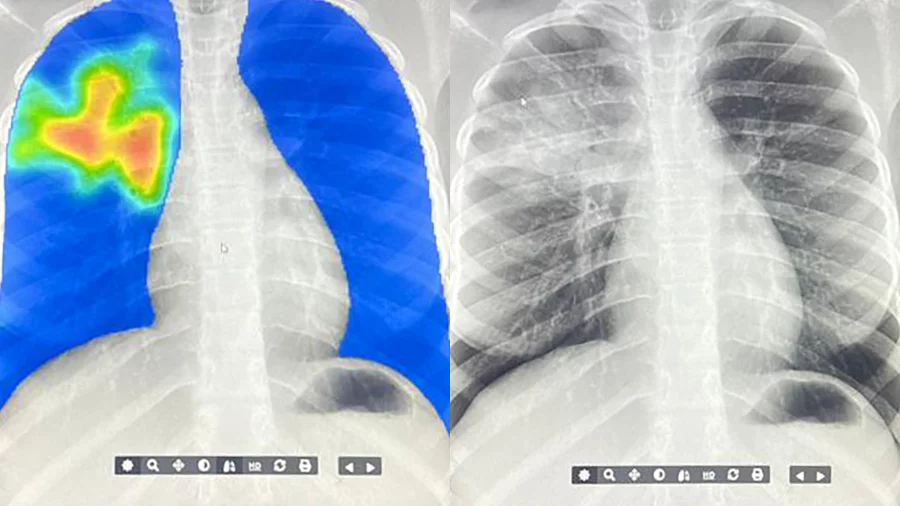

AI is stepping in to detect TB in regions with limited access to radiologists

Tuberculosis is the world’s deadliest infectious disease, with 1.2 million people dying of it each year – roughly 3,500 per day. In remote regions, or areas where there simply aren’t enough radiologists to treat everyone, mobile x-ray machines and AI algorithms are helping to detect this bacterial infection.